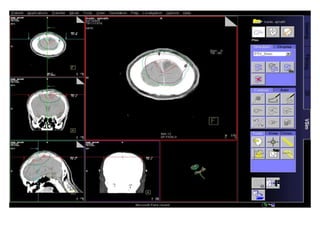

RT planning: meningioma

GTV/CTV = residual tumour / tumour bed for gr II / gr III

CTV = 5 mm for benign meningiomas

2 - 3 cms for high grade meningiomas / HPC

PTV = 2mm for SRT

5mm for 3DCRT

All normal structures contoured

Dosage:

Gr-I:

54Gy/30# conformal RT

25Gy/5# / 13Gy/1#

Gr II & III meningioma:

60Gy/30#/6wks

Conformal RT

Grade I Grade II/III

Tharmoplastic mask

CT scan with contrast- 3 mm slice

MRI scan with T1 contrast & T2 flair is a must

RT planning: meningioma GTV/CTV= residual tumour / tumour bed for gr II / gr III CTV = 5 mm for benign meningiomas 2 - 3 cms for high grade meningiomas / HPC PTV = 2mm for SRT 5mm for 3DCRT All normal structures contoured Dosage: Gr-I: 54Gy/30# conformal RT 25Gy/5# / 13Gy/1# Gr II & III meningioma: 60Gy/30#/6wks Conformal RT Grade I Grade II/III Tharmoplastic mask CT scan with contrast- 3 mm slice MRI scan with T1 contrast & T2 flair is a must